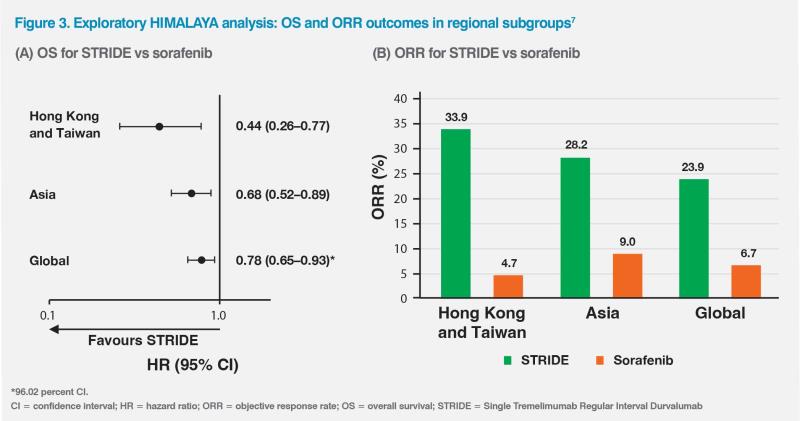

HCC aetiology varies globally and may affect response to immunotherapy.5,6 HBV is the main cause of HCC in most Asian countries, whereas hepatitis C virus or nonviral causes are more commonly associated with HCC in Japan and Western countries.5 An exploratory HIMALAYA analysis (n=479) evaluating the effectiveness of STRIDE vs sorafenib in patients from Asia, excluding Japan, showed a greater magnitude of OS benefit in the Asian subgroup (HR, 0.68; 95 percent CI, 0.52–0.89) vs the global population (HR, 0.78; 96.02 percent CI, 0.65–0.93). Within the Asian subgroup, STRIDE-treated patients from Hong Kong and Taiwan (n=141) were predominantly HBV carriers and had an even greater improvement in OS (HR, 0.44; 95 percent CI, 0.26–0.77). (Figure 3A) Of note, the ORRs among Hong Kong and Taiwan patients were 33.9 percent with STRIDE vs 4.7 percent with sorafenib, while the respective values in the Asian subgroup were 28.2 vs 9.0 percent and 23.9 vs 6.7 percent in the global population.7 (Figure 3B)